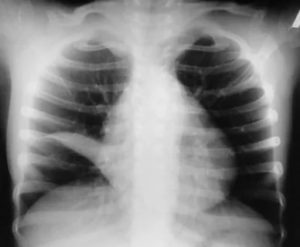

Уточнить наличие ателектаза, его локализацию и объем для определения тактики лечения помогает рентгенологическое исследование органов грудной клетки. Его проводят минимум в двух проекциях. В более трудных случаях, для диагностики случаях прибегают к помощи томографии.

Рентгенологические признаки, позволяющие заподозрить наличие ателектаза:

- Изменение плотности (затемнение) тени сжатого участка легких в сравнении с окружающими ее тканями, часто повторяющей контуры сегмента, доли;

- Изменение формы купола диафрагмы, смещение органов средостения, а также корней легких в сторону ателектаза;

- Наличие функциональных признаков бронхостеноза (необязателен, если механизм ателектаза не обтурационный);

- Сближение теней ребер на стороне поражения;

- Сколиоз позвоночника с направлением выпуклости в сторону ателектаза;

- Полосовидные тени на фоне неизмененных участков (дисковидный ателектаз) легких.

На первом этапе принято делать обзорную рентгенограмму органов грудной полости. Она представляет собой суммарное изображение всей толщи тканей, расположенных внутри груди, при этом тени одних деталей в той, или иной мере наслаиваются на тени других.

Ателектатическое легкое не наполняется воздухом, и на рентгенограмме выглядит как однородная тень. Существует также ряд дополнительных признаков, позволяющих определить ателектаз:

- Легкое уменьшено.

- Органы средостения смещаются в сторону поражения.

Считается, что данных признаков достаточно, чтобы достоверно поставить диагноз «спавшегося легкого» при проведении рентгенографии, томографии и фибробронхоскопии. Однако, смещение органов в сторону поражения на фоне обширного затемнения легочного поля также может наблюдаться при фибротораксе с циррозом легкого.

Рентгеновский снимок ателектаза легких

При проведении рентгенологического исследования на рентгенограммах определяется тень, имеющая четкие вогнутые границы. При проведении рентгеноскопии у пациентов с ателектазом легкого можно выявить симптом Якобсона-Гельцнехта (толчкообразные смещения тени средостения, направленные в сторону поражения).

Рентгенограмма грудной клетки при ателектазе верхней доли правого легкого (прямая проекция): верхняя доля правого легкого уменьшена в объеме, гомогенно затенена.

Общеизвестно ,что ателектаз в классических случаях характеризуется гомогенным затемнением , строго ограниченным анатомическими границами и определенными функциональными симптомами Уменьшение спавшегося сегмента или доли ведет к компенсаторному расширению соседних отделов легкого , изменению формы и положения лобарных границ При большей степени спадения легочной паренхимы отмечается смещение тени и органов средостения в сторону поражения , перемещение корня легкого ,подъем купола диафрагмы ,сужение межреберных промежутков и т.д.